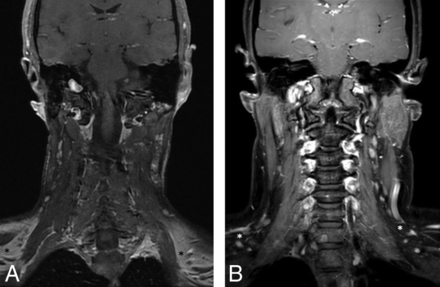

Gadolinium-enhanced coronal T1-weighted MR images with SPIR (A) and mDixon (B) techniques for fat suppression. Note incomplete fat suppression (dark asterisk) in the supraclavicular regions on the SPIR technique and complete uniform fat suppression (white asterisk) in similar regions on the mDixon technique.